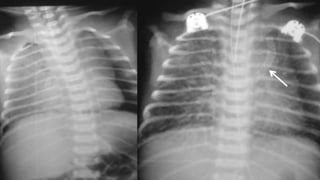

OBSTRUCTED TAPVC

• CXR

✦ Plethoric Lung Fields / Ground

Glass appearance

✦ Absence of cardiomegaly

✦ Indistinct cardiac silhouette

• DDX

✦ Meconium Aspiration

✦ Hyaline Membrane Disease